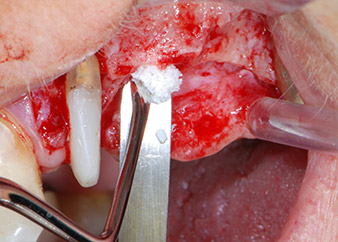

Prior to implant placement, and following verification of an intact Schneiderian membrane (Fig. 9), the internal sinus floor was augmented at both implant sites by means of xenogeneic bone substitute material (Bio-Oss, Geistlich Biomaterials) (Fig. 10).

Bone deficiencies around the implants, at the mesial aspect of tooth 27 and around the buccal root of tooth 24, were filled with xenogeneic bone substitute particles and covered with an absorbable collagen membrane (Bio-Gide, Geistlich Biomaterials) for GBR augmentation (Figs. 13 and 14).